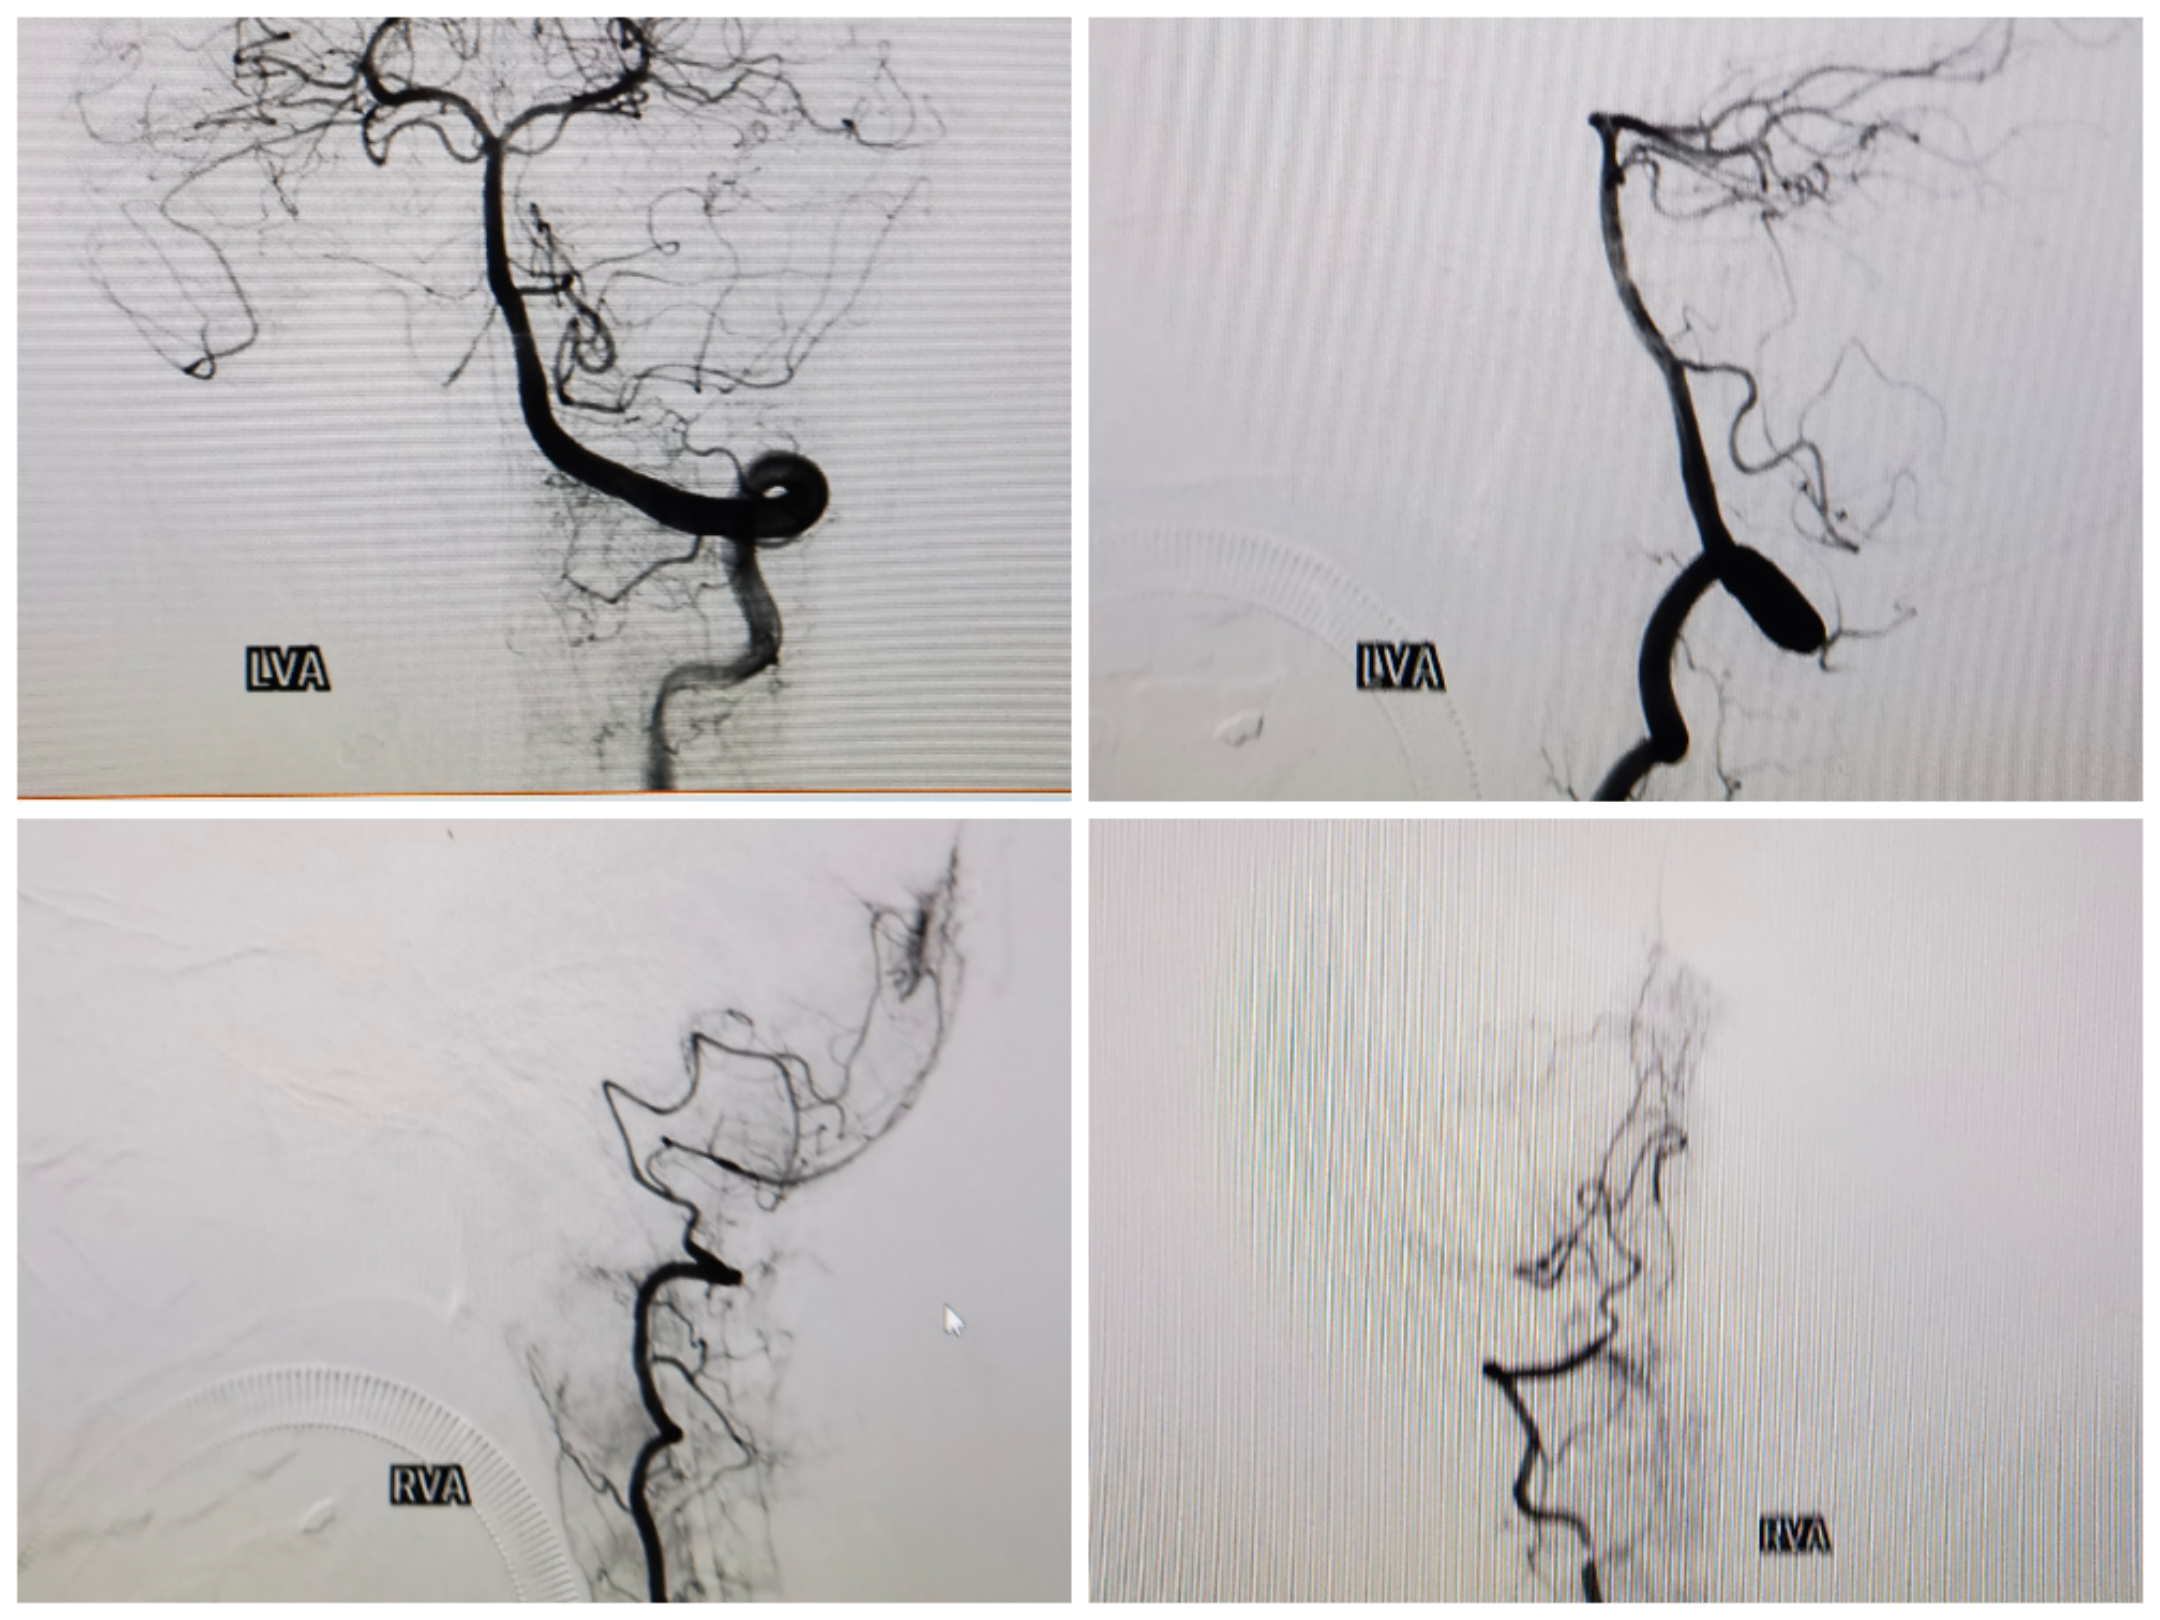

双椎造影无特殊

双侧颈内造影

3D重建情况